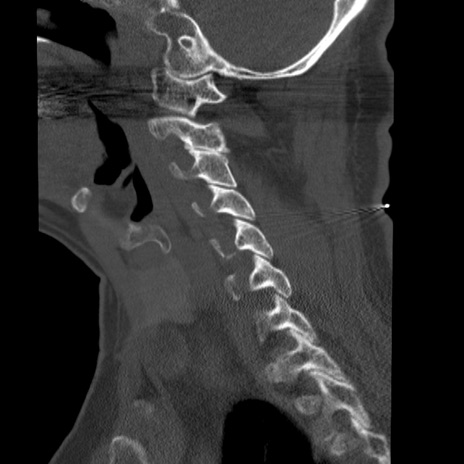

症例50 頚椎CT(矢状断像)

【症例】60歳代女性

【主訴】後頭部〜右後頸部にかけての痛み

【現病歴】本日飲食店でコーヒーを飲んでいたところ、突然後頭部〜右後頸部にかけて痛みが出現し、右上肢の感覚障害を伴ったため救急要請。

【身体所見】脳神経学的に明らかな異常所見を認めず。右上肢に軽度の感覚障害あり。

異常所見と診断は?

頚椎CT